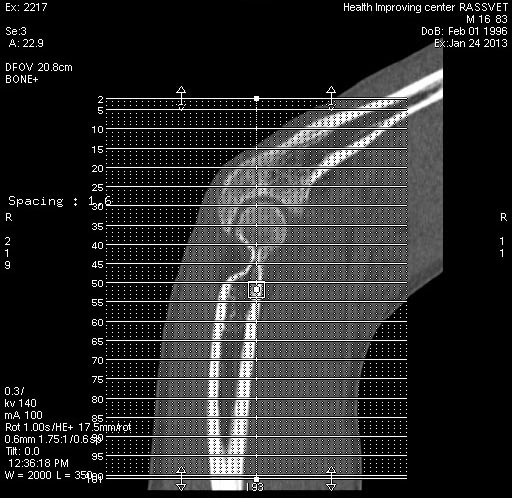

Добрый день колеги.  Обратился больной 16 лет. Травма три  месяца назад.

На соревнованиях по дзюдо упал на пр руку. В районной ЦРБ произведена

рентгенография локтевого сустава - костной патологии не выявлено. На две

неделе наложена гипсовая лонгета. Проводилась ФТЛ (со слов больного - по

всей видимости озокерит) и ЛФК. В данный момент обьем движений сгибание

80 гр. Рзгибание 110 гр. Сделали КТ ниже внутреннего надмыщелка выявлен

свободный фрагмент. Неврологии нет. Стоит ли удалять. Курс ФТЛ и ЛФК без

эффекта.